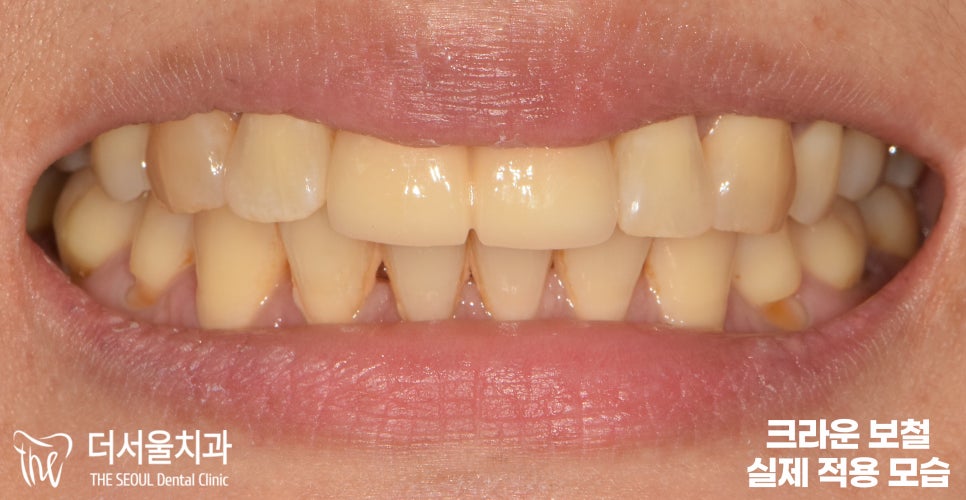

지르코니아 크라운 보철을

실제로 적용한 모습을 보여드립니다.

옆에 있는 다른 이들과 비교해도

크게 티가 나거나 어색함이 없죠?

이렇게 자연스럽게 잘 세팅되면,

일상 생활에 있어 전혀 문제될 것없이

예전에 했던 생활 그대로 이어나갈 수 있습니다.